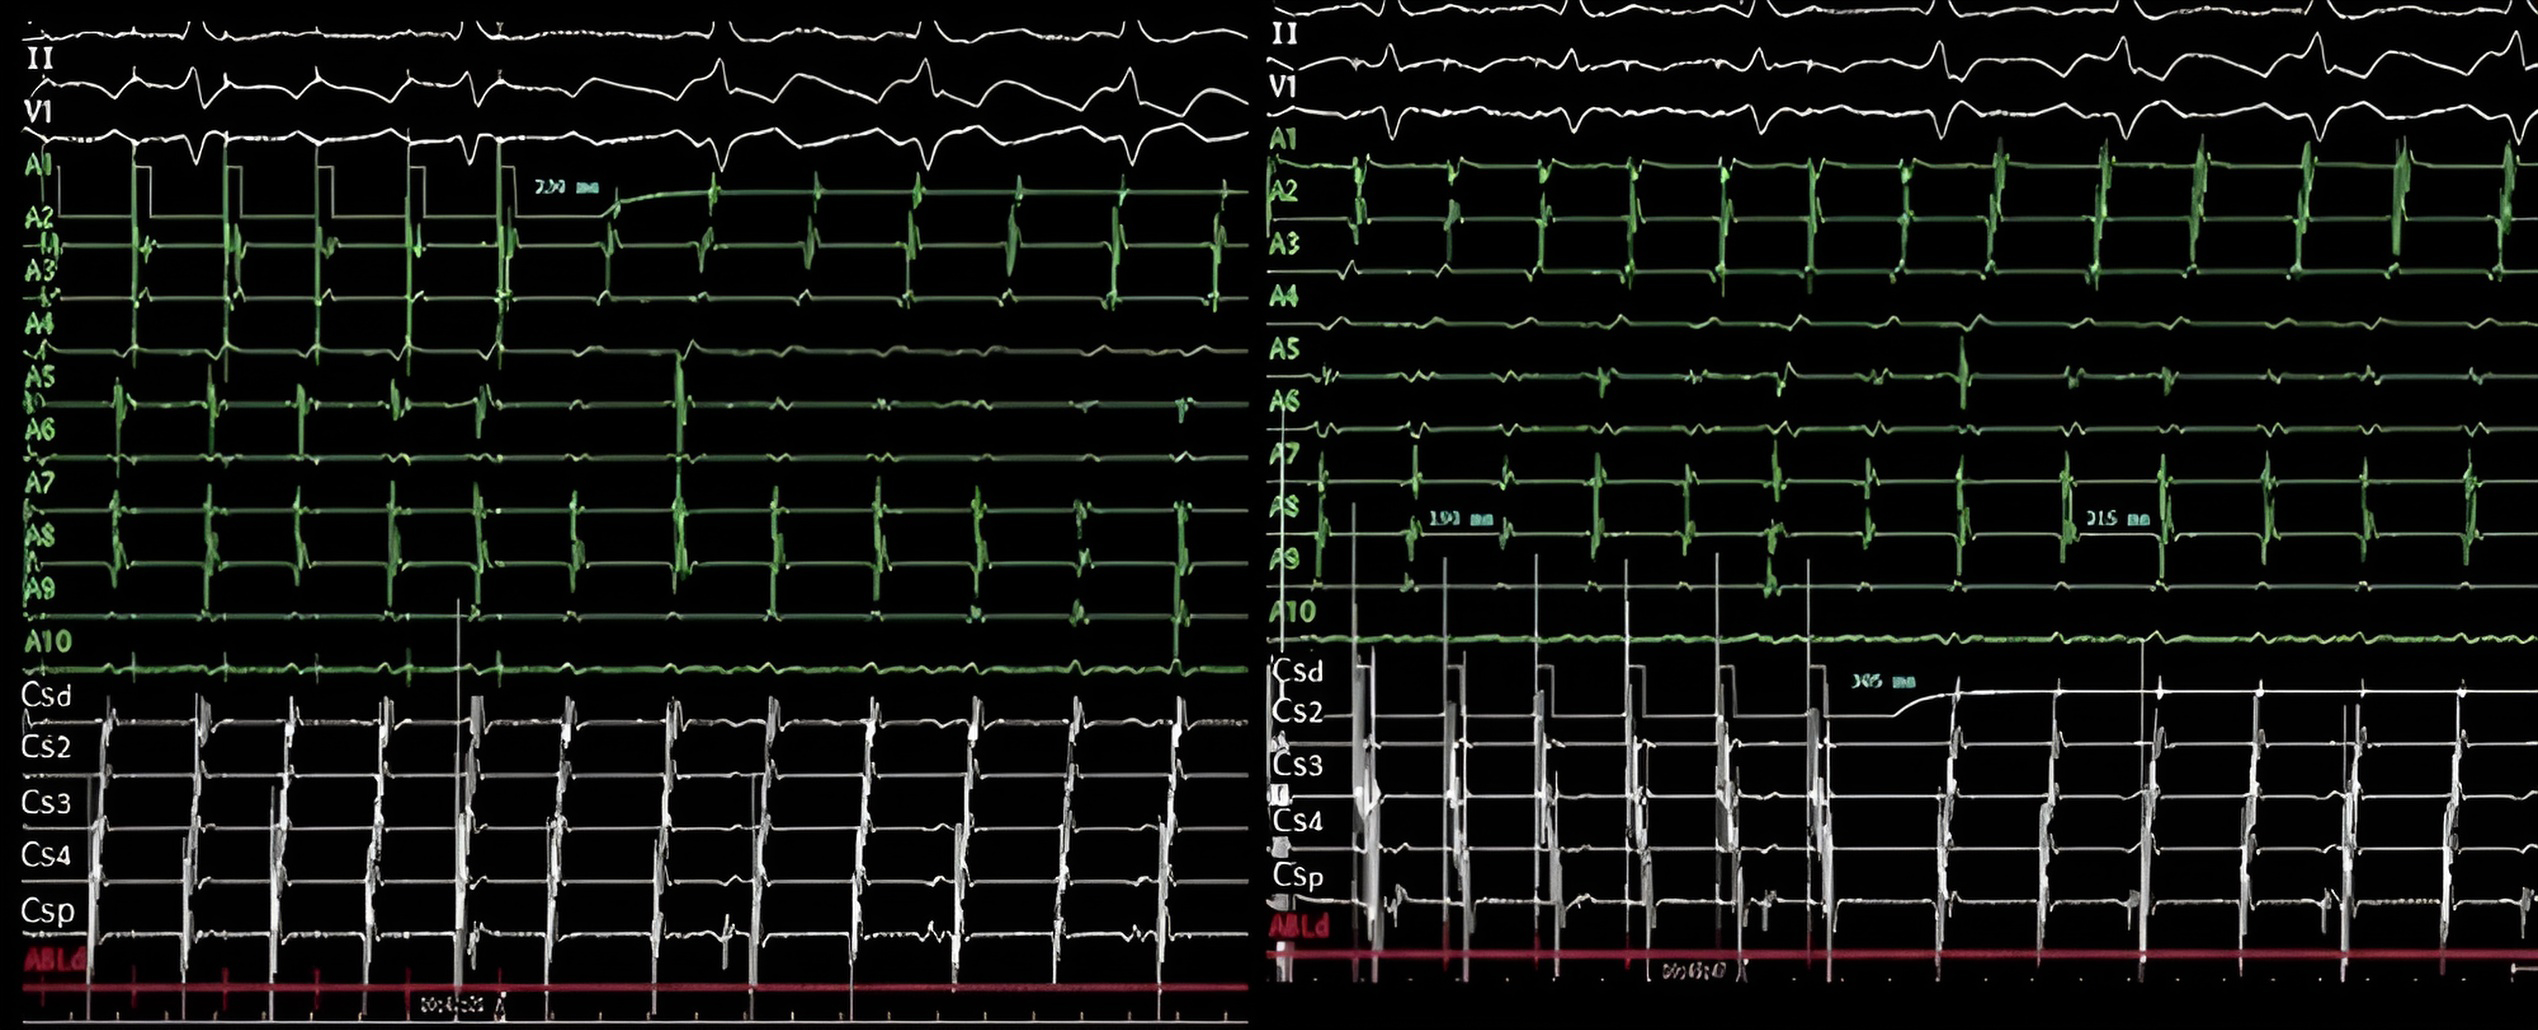

Ablation can be performed in sinus rhythm or during flutter (Fig. 6). If electrocardiogram (ECG) is typical and the patient has no history of cardiac surgery or previous ablations, CTI ablation can be performed directly in sinus rhythm without induction. However, in patients with previous cardiac surgery or non-completely typical ECG, it is necessary to confirm the involvement of the right atrium and the CTI in the circuit using pacing mapping techniques during spontaneous or induced atrial flutter [95, 96, 97].

Fig. 6.Electrocardiographic and electrophysiological tracings in typical atrial flutter. Left panel: Surface ECG of counterclockwise flutter with 2:1 ventricular conduction. Right panel: Endocavitary tracings of a counterclockwise flutter showing in the recordings from duodecapoles catheters relatively fast caudocranial activation of septum (pairs A10 to A7) followed by superior part of RA (A6-A5), lateral wall (A4-A1) and finally CTI (ABLd). LA is activated proximal to distally, secondarily from this circuit (coronary sinus tracings CSp to CSd). ECG, elcetrocardiogram; CTI, cavotricuspid isthmus; LA, left atrium; RA, right atirum; CSp, proximal coronary sinus; CSd, distal coronary sinus.

As part of the standard entrainment protocol for atrial flutter, pacing with a cycle length less around 30 ms less than flutter one, from the CTI is commonly employed, causing transient acceleration of the flutter to the pacing rate, but without modifying the F-wave morphology in the surface electrocardiogram, nor the morphology and sequence of atrial electrograms (concealed fusion, see Fig. 7) [98]. Following pacing cessation, the atrial flutter continues at its baseline frequency, and the post-pacing interval is measured from the last pacing artifact to the first unstimulated electrogram recorded at the pacing site (Fig. 7). This interval represents the time required for the impulse to reach the circuit, complete one full revolution inside it and return to the point of pacing. If the difference between the post-pacing interval and the atrial flutter cycle length is less than 30 ms, the involvement of the CTI in the arrhythmia circuit can be ensured [99, 100].

Fig. 7.Use of entrainment techniques to define the involvement of structures in the flutter circuit. Left panel. Intracavitary recording during entrainment of a typical atrial flutter patient. Pacing from the low lateral wall of the right atrium (A1). Upon cessation of stimulation, the time until the next beat (postpacing interval), is 230 ms, almost identical to the cycle length of flutter (215 ms). This indicates that this point is part of the circuit of the tachycardia. Right panel. Pacing at a cycle length of 190 ms from the pair of electrodes furthest from the electrode located in the lateral wall of the left atrium. Upon cessation of stimulation, the time until the next atrial electrogram is 305 ms, notably longer than the cycle length of flutter (215 ms). As opposed to the previous example, this point is not part of the circuit and is very distant from it. Note that in the left panel, the morphology and sequence of atrial electrograms from both the 20-pole and the coronary sinus catheters are identical during entrainment and during tachycardia (concealed fusion). On the right side, they are very different, being during entrainment a mix of pacing and intrinsic beats (manifest fusion). CSp, proximal coronary sinus; CSd, distal coronary sinus.